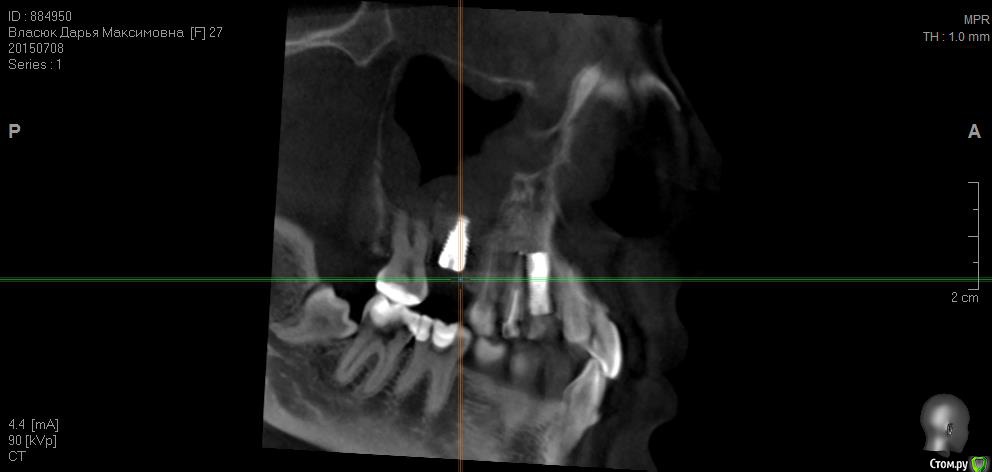

fifa888.dexo Опубликовано 22 июля, 2015 Автор Поделиться Опубликовано 22 июля, 2015 а это все что я могла придумать с кт Ссылка на комментарий

diesel87 Опубликовано 22 июля, 2015 Поделиться Опубликовано 22 июля, 2015 http://fs2.directupload.net/images/150723/9sv48h7l.jpg http://fs1.directupload.net/images/150723/9nsd29hm.jpg http://fs2.directupload.net/images/150723/q4s456ou.jpg http://fs2.directupload.net/images/150723/9x7h27mc.jpg По КТ:1.возможно имплант в области клыка в апексе (самой верхней части) контактирует с четверкой (не ясно из-за того что имплант фонит), если четверка не реагирует, то пока наблюдать, делать прицельные снимки раз в 3/6/9/12 месяцев.2. Не докрученный формирователь, особо не страшно, но в щель может врасти десна, будет запах, локальное воспаление в области шейки импланта, так что лучше его докрутить или если он упирается в соседние зубы, поменять на узкий и докрутить.3. Имплант что в синусе, по снимку он практически весь в кости, а "воспаление" могло быть там и ранее, есть снимки до операции?? Ссылка на комментарий